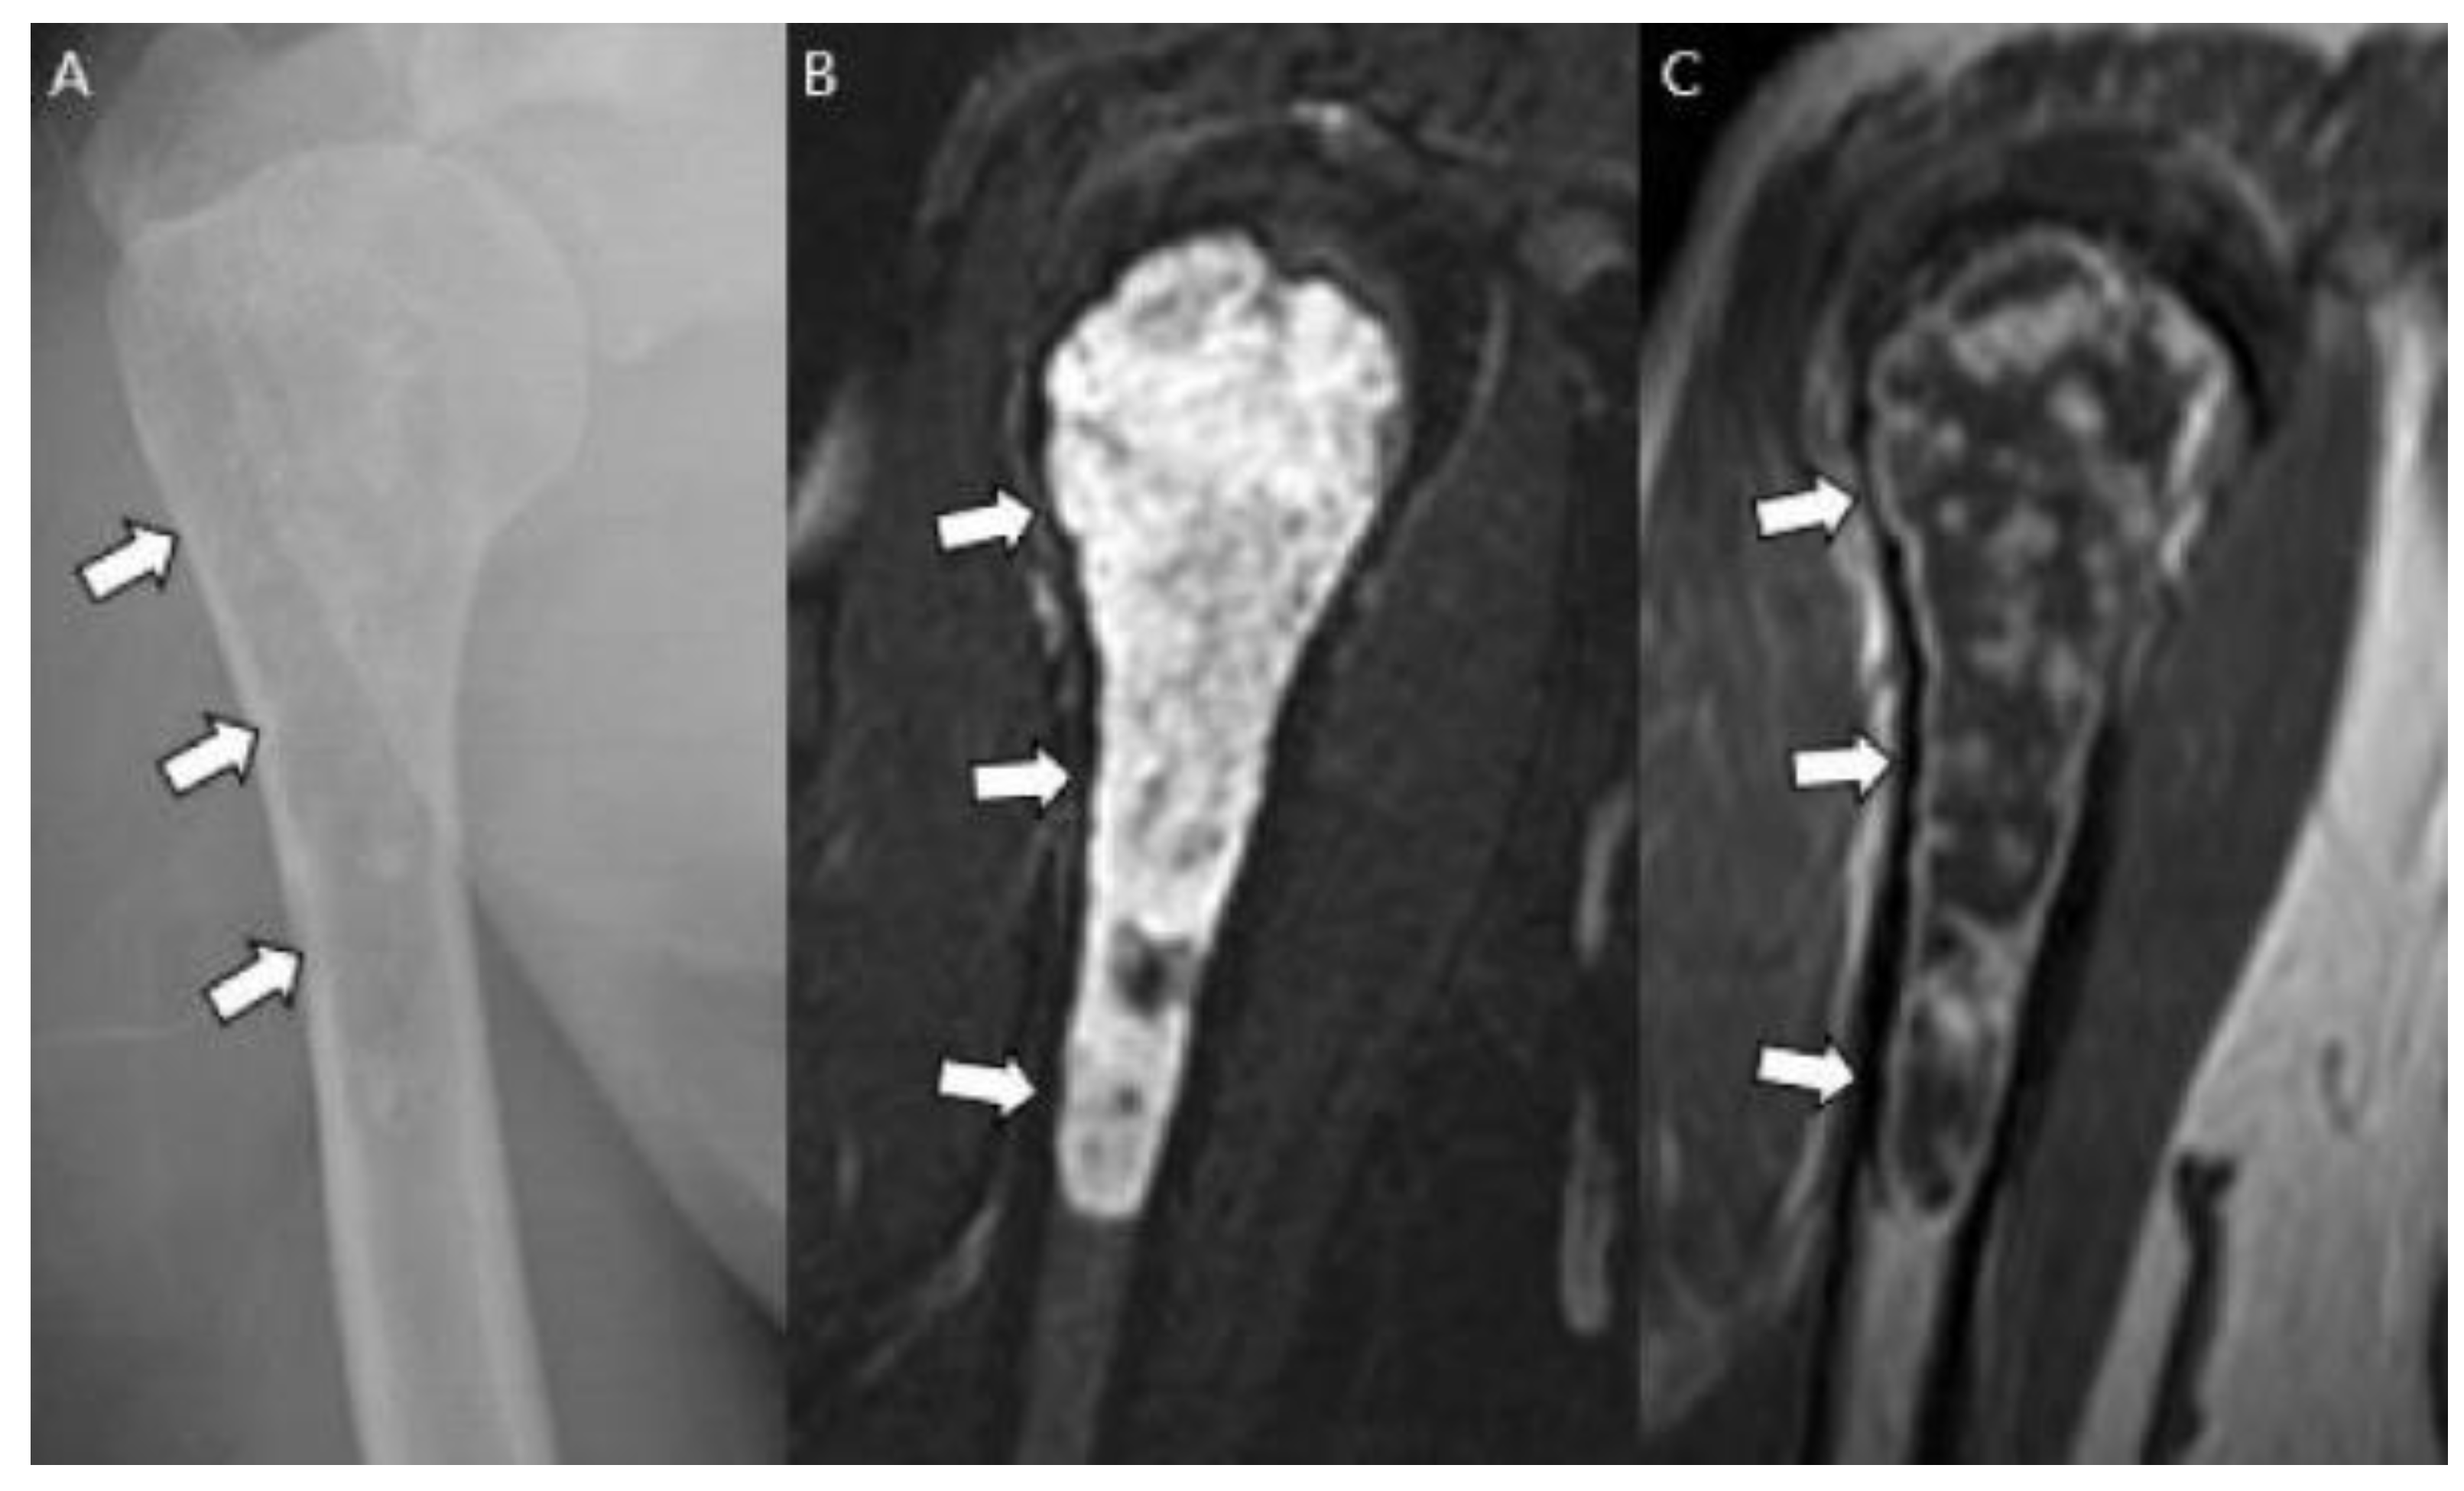

Sensitive radiographic features differentiating enchondromas from chondrosarcomas include deep endosteal scalloping ≥2/3 of the normal cortical thickness [5,15] (Figure 3). Extensive longitudinal endosteal scalloping over ≥2/3 of the lesion length is also strong evidence of chondrosarcoma (although a somewhat less reliable criterion) [1,24] (Figure 4).

Figure 4.

A typical cartilaginous tumor of the humerus in a 43-year-old woman. (A) Radiographs reveal a mixed lytic and sclerotic lesion in the humerus (arrows) with typical ring-and-arc calcifications. (B) Coronal T2-weighted image with fat suppression and (C) T1-weighted enhanced image demonstrate a lobulated chondroid tumor with longitudinal endosteal scalloping (arrows) along the 9 cm length of the tumor.